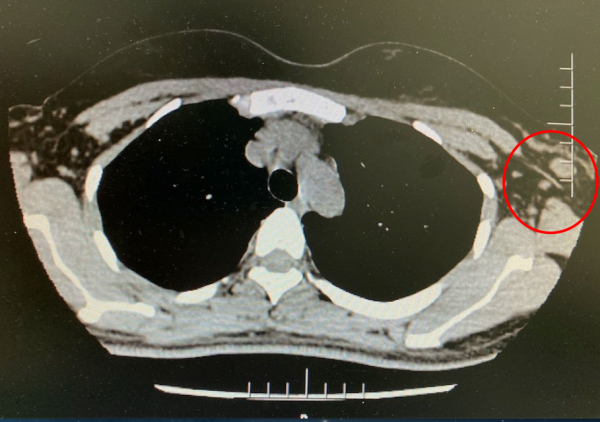

肺部CT:左乳上象限腫塊影及左側腋窩淋巴結腫大,雙肺未見佔位病變(圖2)。